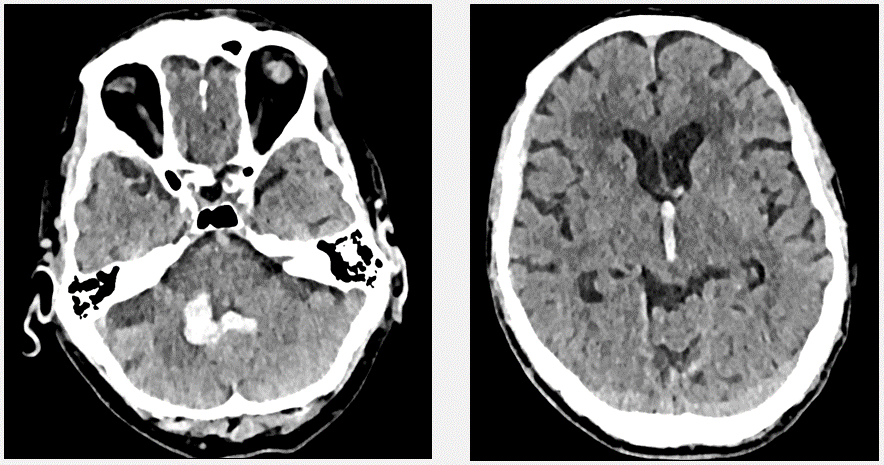

Varón de 83 años

HTA, antecedentes de vértigos de repetición, hipoacusia y acúfenos

Activación de código ictus, porque tras levantarse comienza con pérdida de audición brusca en OD, parestesias en hemicara derecha, diplopia, disartria y mareo con inestabilidad, sensación de giro de objetos y vómitos.